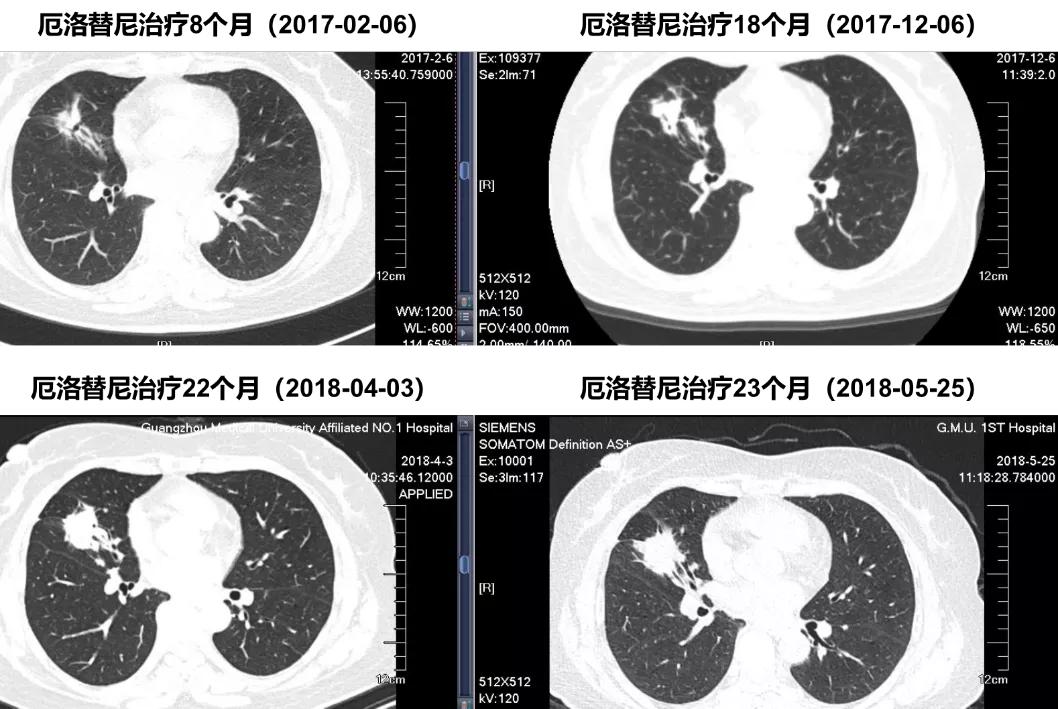

治疗期间疗效持续PR,2018.05胸部CT显示右中肺病灶增大,提示疾病进展,持续服用厄洛替尼至7月,PFS1=2年

胸部CT显示:在2018.04.03右中肺靶病灶略增大,5.25 CT示持续增大。

阿美替尼二线治疗患者CT随访

胸部CT显示:阿美替尼治疗1个月后,疗效达到PR,且后续治疗过程中,病灶持续好转。